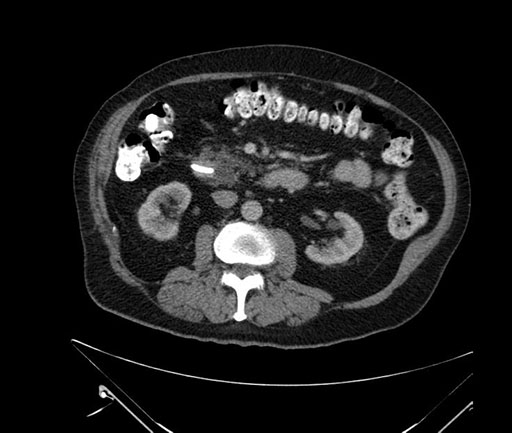

Imaging Analysis

Look through the patient's CT scan to identify any areas of concern for the necessary procedure.

Based on your CT findings, which issue(s) would give reason for "planned slowing down moment(s)" in this case?